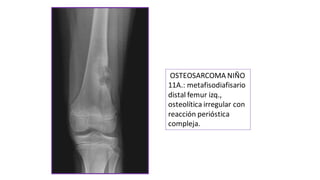

OSTEOSARCOMA NIÑO

11A.: metafisodiafisario

distal femur izq.,

osteolítica irregular con

reacción perióstica

compleja.

OSTEOSARCOMA NIÑO 11A.: metafisodiafisario distalfemur izq., osteolítica irregular con reacción perióstica compleja.